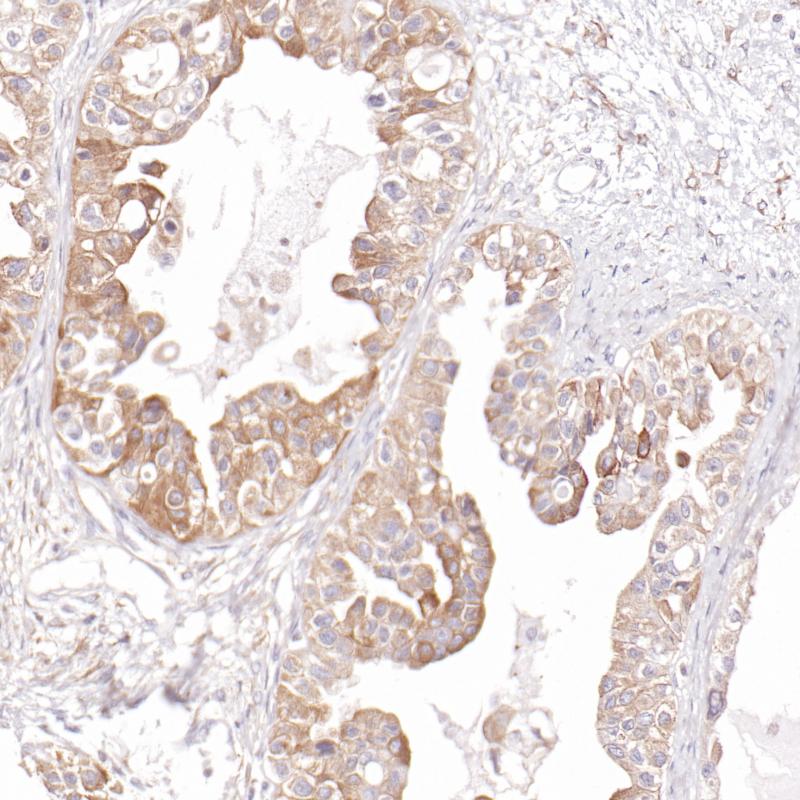

胎盘hCG beta(BP6198)染色

hCG beta是人绒毛膜促性腺激素(hCG)的亚基。hCG是一种复杂的糖蛋白,由两个糖基化亚基α和β组成,它们是非共价键结合的。α亚基与垂体促性腺激素(LH, FSH和TSH)中的亚基相同。亚单位是不同的每一种激素和赋予受体和生物学特异性。在怀孕和母亲适应中起着至关重要的作用。刺激卵巢合成维持妊娠所必需的类固醇。

目录号

BX50221

克隆号

BP6198

阳性对照

胎盘

亚细胞定位

细胞质

组织类型

FFPE

修复方式

HIER

稀释比

1:100-1:200

规格

100μl/vial, 1ml/vial

用途

RUO